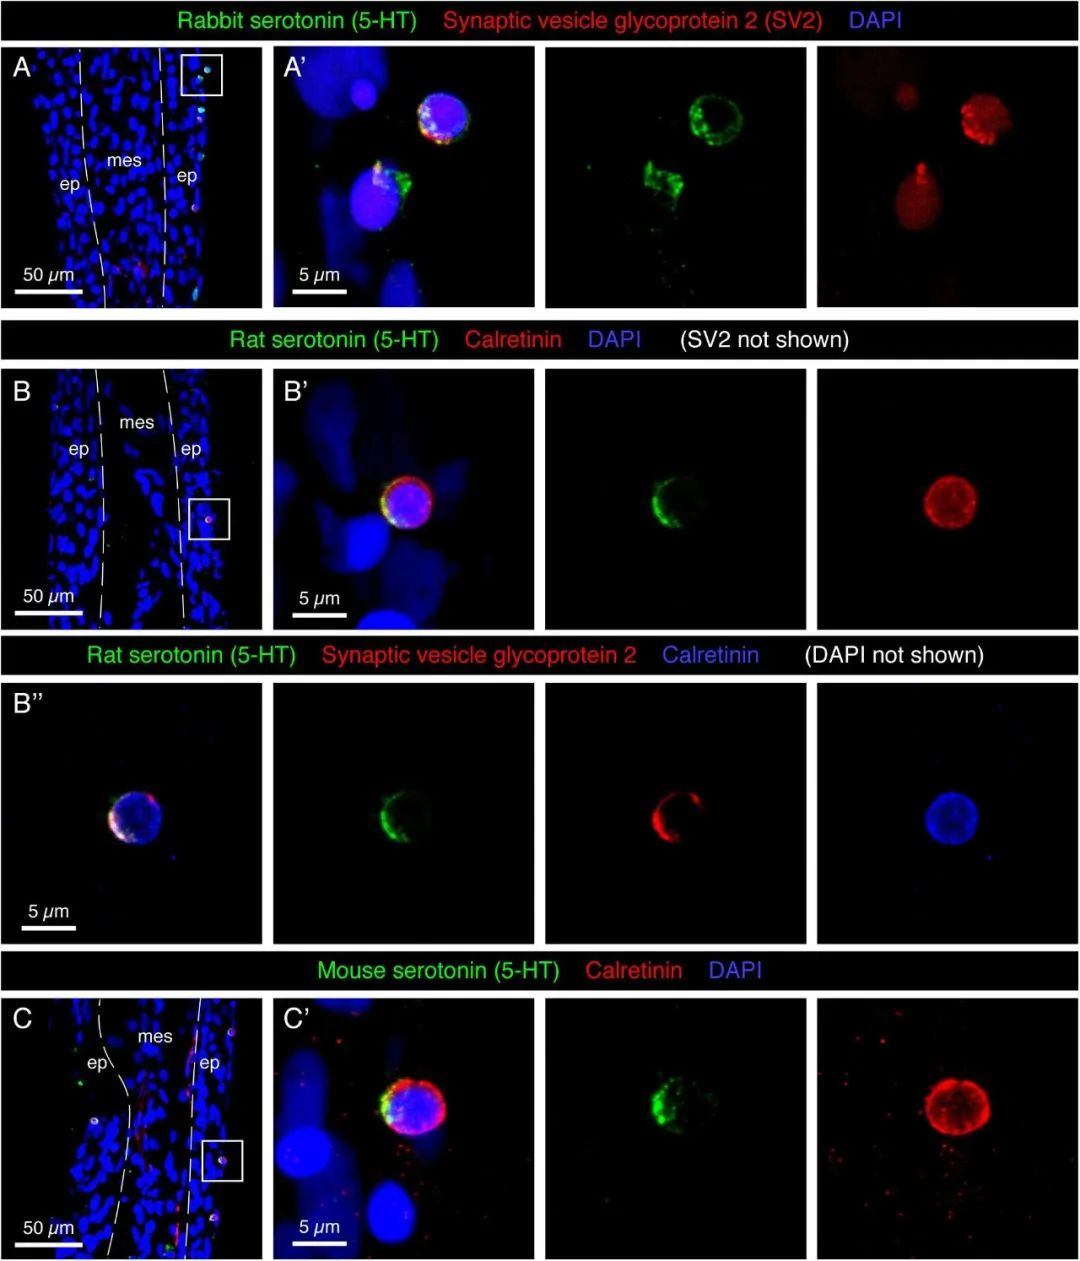

论文图表排版

滑动查看更多 点击查看大图